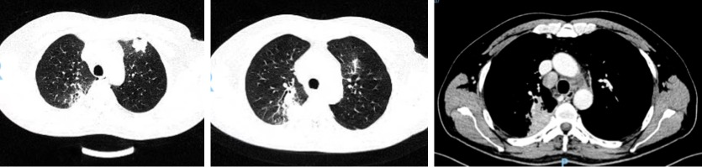

胸部增强CT(2024-06-05):双上肺实变,颈部及纵隔淋巴结肿大。